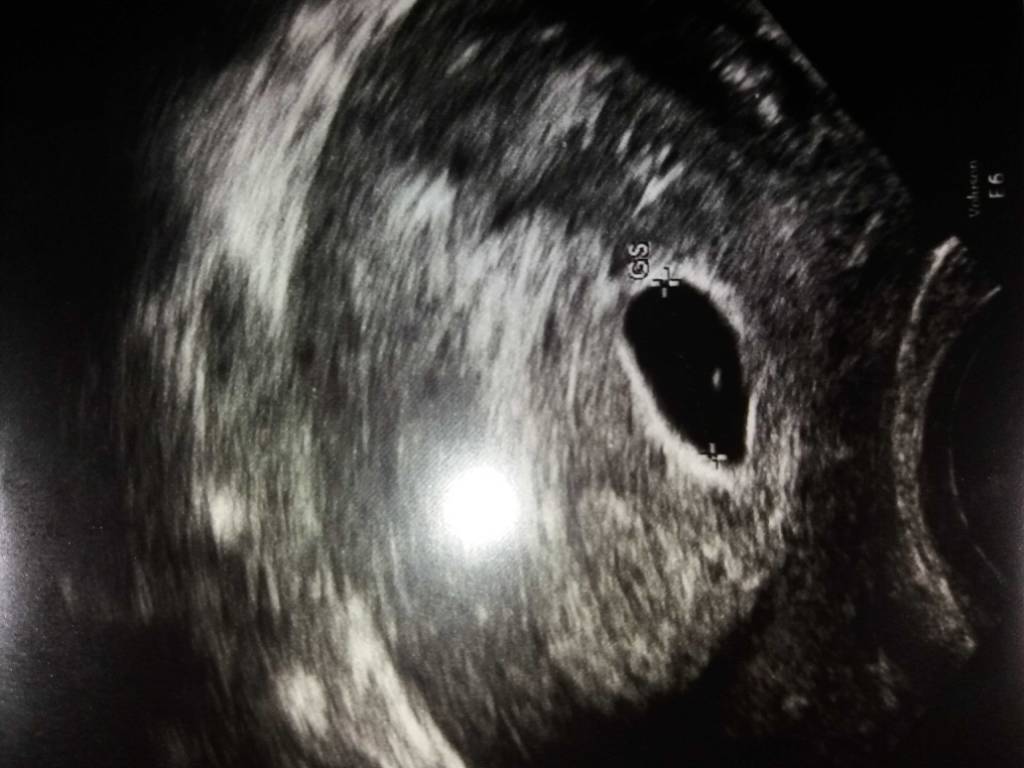

Dziewczyny dziekuje za mile slowa, martwi mnie tylko wielkosc tego pecherzyka zoltkowego w stosunku do wielkosci pecherzyka ciazowego... Ogladalam zdjecia na Google u wydaje mi sie ze powinien byc on juz bardziej widoczny z zarysowanym ksztaltem a nie taka mala kropeczka jak u mnie...Boje sie ze jednak jest za maly o nie zdola odzywic zarodka

Pamietacie jak to bylo u Was moze?Zobacz załącznik 874347